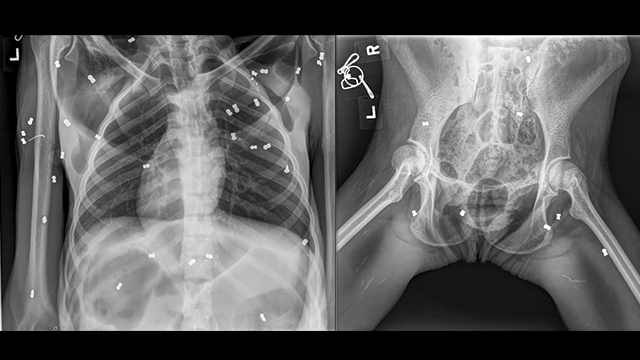

In addition, X-ray result shows 74 pellets spread in her body, broken left Clavicula bone (the bone tear up the skin), broken left pelvic with crack more less two centimeters.